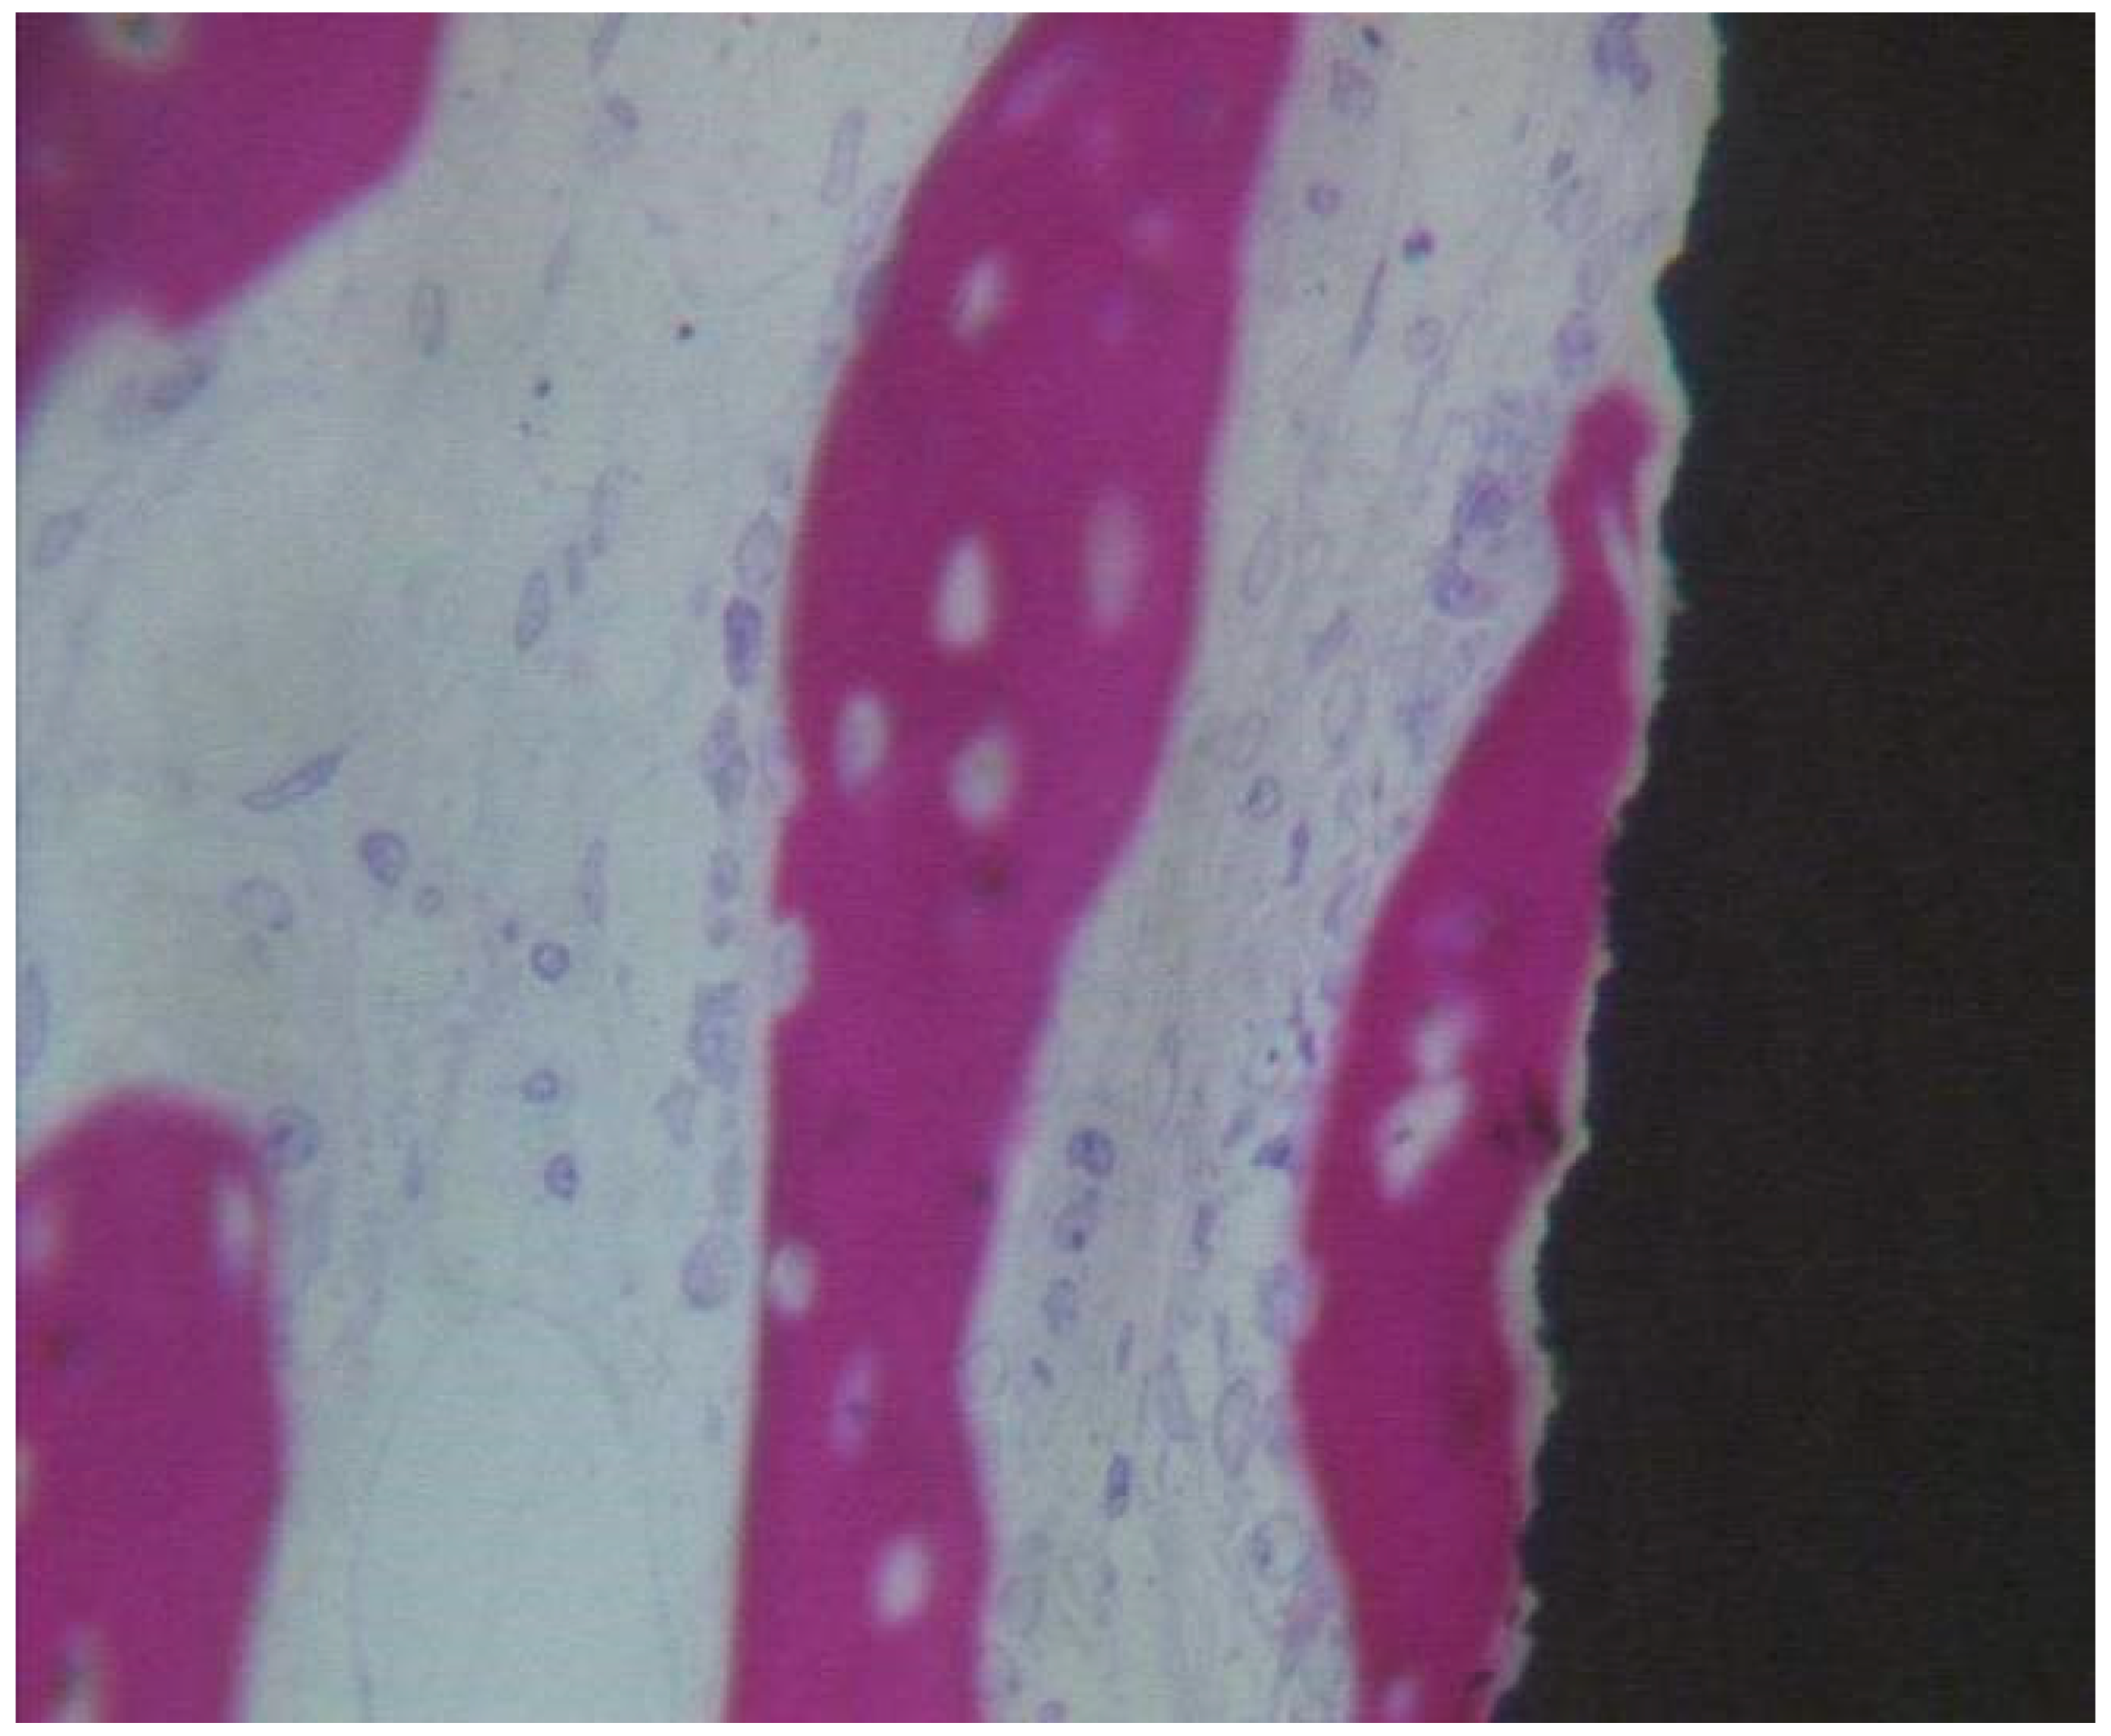

Coated Implant Surface